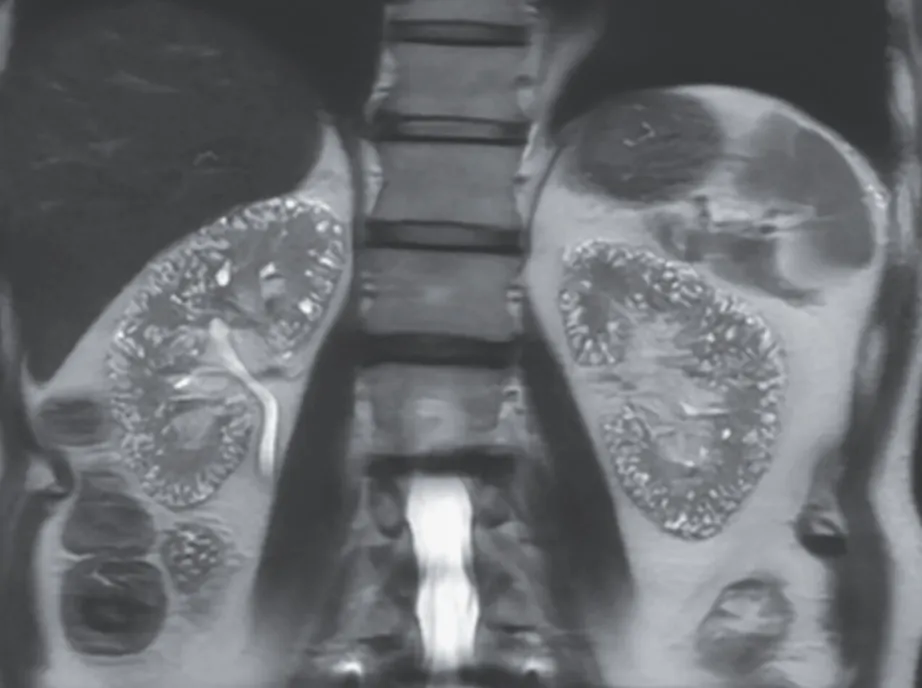

O paciente negava qualquer histórico familiar de doença renal cística. A RM ponderada em T2 revelou numerosas microcistos localizados no córtex e na medula de ambos os rins (Imagem abaixo - Painel A, corte axial; Painel B, corte coronal).

Foi feito o diagnóstico de microcistos compatíveis com nefropatia induzida por lítio. O uso de lítio está associado a diversos efeitos nefrotóxicos, incluindo diabetes insipidus nefrogênico, acidose tubular renal e nefropatia túbulo-intersticial crônica.

Microcistos de 1 a 2 mm podem ser observados em exames de imagem em pacientes com nefropatia túbulo-intersticial crônica induzida por lítio. O paciente permaneceu em tratamento com agentes alternativos para o transtorno bipolar. Após 2 anos de seguimento, a função renal manteve-se estável.